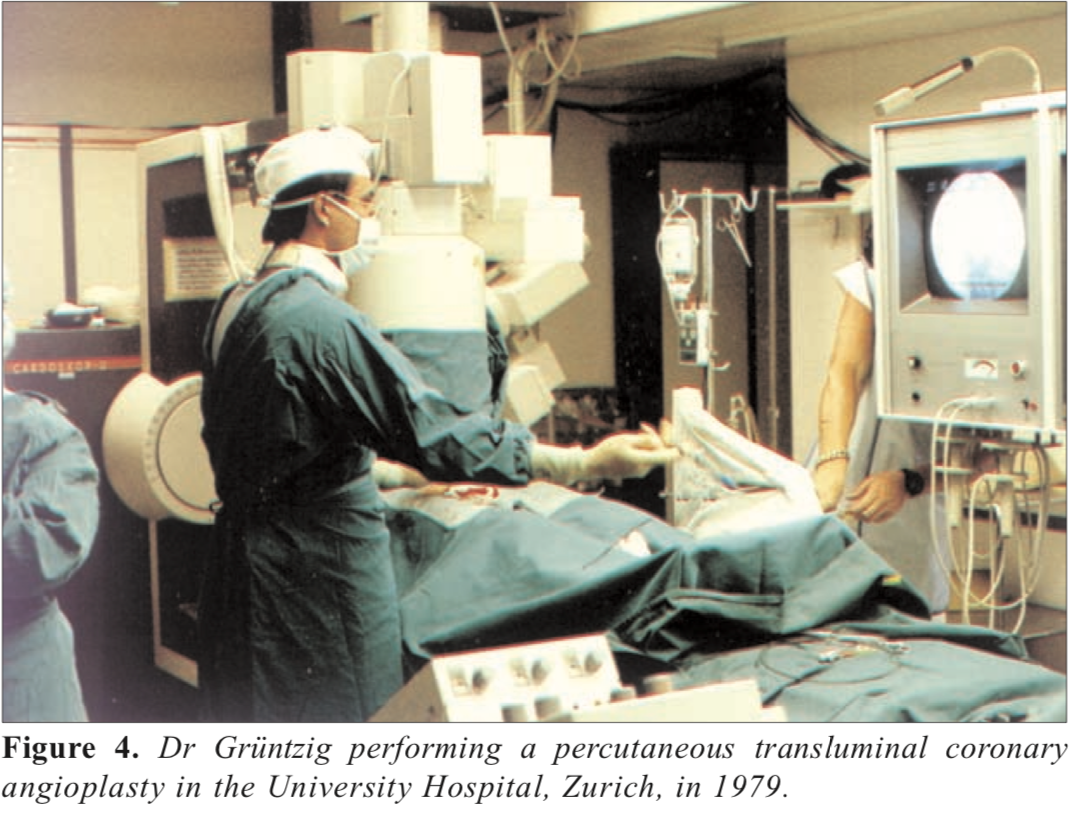

Andreas Grüntzig - 1977: First Coronary Angioplasty - bio - AHA Circulation - 2007

Andreas Gruentzig: The Teaching Genius - article by J. Willis Hurst